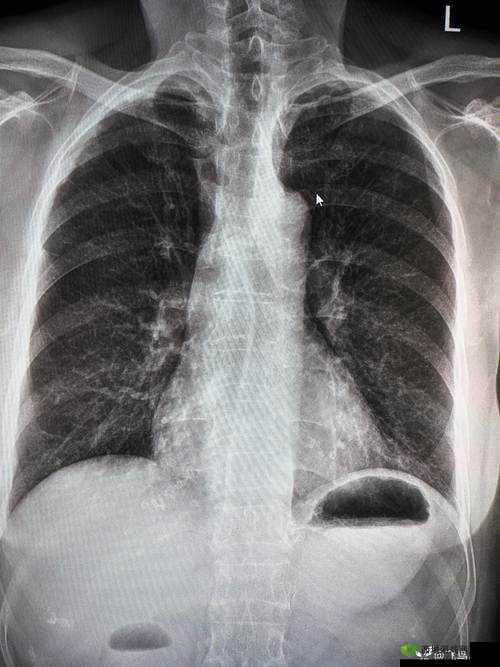

在医学领域,胸片是一种常见的检查工具,用于检测肺部疾病和异常。你是否曾想过,当胸片被 100%曝光时,会呈现出怎样的惊人景象?最近,一组名为“胸片 100%曝光下那愤怒的情绪震撼呈现”的照片在网络上引起了轰动。这些照片展示了在极度愤怒的情绪下,人体肺部的变化,让人不禁对情绪与健康的关系有了更深刻的认识。

这组照片的创作者是一位资深的医学摄影师。他花费了大量时间和精力,通过特殊的技术手段,将胸片 100%曝光,从而揭示了情绪对人体的影响。在这些照片中,我们可以看到,在极度愤怒的情绪下,肺部的纹理变得异常清晰,甚至出现了明显的扭曲和变形。这是因为愤怒情绪会导致人体内分泌系统的变化,进而影响肺部的功能。